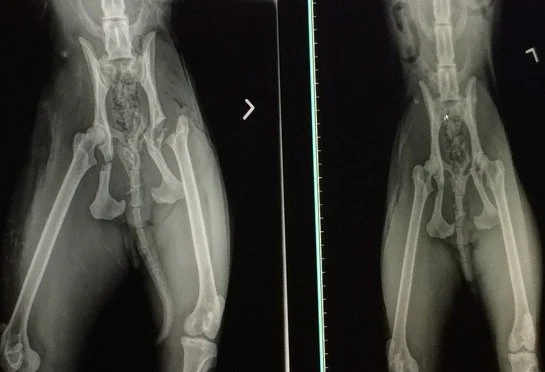

While I was driving the bobcat from the far side east side of Winter Haven to the far west side of Tampa, Jamie Veronica, our President, was frantically trying to arrange for vet care on a Saturday afternoon.  She called on her husband, Dr. Justin Boorstein to help on his day off, she called our primary vet, Dr. Wynn to see if we could use her clinic and if she was around and she called Blue Pearl.  Dr. Wynn had a full day of clients but agreed to let us bring the little bobcat, who weighed in at a mere 16.2 pounds, to the Ehrlich Animal Hospital.  L-R  Dr Liz Wynn, Jamie Veronica, Cypress the bobcat, Dr. Justin Boorstein.  Dr. Wynn ascertained from the physical exam that Cypress had no broken legs, but that her pelvis felt like it was crushed.  This was about the worst news we could get, so she sent the yearling bobcat kitten in for -rays.  Here Ben, a tech at Ehrlich Animal Hospital, is putting lube in her eyes to protect them while the bobcat is sedated and then she is put on anesthesia gas.  Dr. Boorstein holds the anesthesia mask over the bobcat kitten's nose while Ben shaves her forepaw to insert a catheter to give her fluids and medication.  Her blood work looked good, with no cat diseases that would prevent her release, so we continue.  Cats in general have an amazing ability to heal themselves.  The bobcat arrived with a bleeding toe and a puncture wound above her eye, and road rash on her joints as she bounced along the pavement after the impact, but the toe wound has already disappeared completely.  Dr. Justin is cutting away the ravaged edges of her wounds and closing them with skin glue.  The bobcat's temperature was only 92 degrees and should have been about 100-101 so she is on a full body heating pad, has warmed water bottles snuggled up to her and a thick blanket over the top to keep her from going into shock.   Jamie holds the mask over the bobcat's face so the vets and techs can do their work.  The bobcat has a seriously deep puncture wound right above her eye.  She was very lucky not to loose the eye but we aren't sure what caused this.  It seems unlikely that any part of a car hitting her would cause this kind of puncture, so maybe she did it scurrying away from the scene when she bellied under a barbed wire fence, but bobcats are usually tougher skinned than that.  Maybe it is what led to her being in the highway in the first place.  Right next to the scene were bulldozers plowing down her forest.  She's obviously a youngster and most like being pushed out of this territory by her mom and siblings, so it could have been a battle over territory that sent her running for the other side of the highway, where she got smashed by a car.   The results of the x-rays showed that her pelvis was crushed by the impact.  It is broken in 4 places and 2 of them are places that will be very difficult, if not impossible to plate and pin.  We consulted with orthopedic specialists, Dr. Hay and Dr. Salas, and both are telling us that two of the breaks are pretty "easy" to fix, but the other two are just about impossible to plate, so what they often suggest, with cats, is cage rest in the hopes that the cat will remain calm enough to let the bones mend back together on their own. Just judging from the x-rays, the vets fear that even if they can do extensive reconstruction of her pelvis that she may never be whole enough to hunt.  That was the beginning of an emotionally painful decision that we have to make; ie, should we euthanize her so that she doesn't have to go through surgery, recovery and then likely live her life in a cage, or do we do every thing we can surgically, hope for a miracle in her own healing abilities, since she is young, strong and has a vicious will to survive, and then see how she does over the next few months?  These are such tough decisions because we could put her through all of this only to end up with her life being one of captivity that she will probably hate because she has known what it was like to roam for miles, choose her own favorite hunting and sleeping spots and everything else that comes from living free.  I hate having to make these decisions and rely on the advice of our vets and Jamie's sense of fairness to the cat.  For now our plan is to take her in for more x-rays, and probably surgery if that is deemed best by all involved for the cat.  The black on her tooth is just dirt.  Dr. Justin was checking to be sure her jaw was not broken and that no teeth were broken from the impact.

Cypress the rehab bobcat was taken to Blue Pearl today where Dr. Salas (same doctor who did Tonga's surgery) performed a FHO - Femoral Head Ostectomy. You can read more about the procedure here: https://en.wikipedia.org/wiki/Femoral_head_ostectomy She is recovering in the cat hospital and we hope that after 6-8 weeks of cage rest she will show enough improvements to be considered a candidate for release.  During these 6-8 weeks she must be kept in small quarters in the cat hospital and it is imperative that she remain calm.  What happens for Cypress the bobcat will largely depend on her.  We will watch her progress and her demeanor and as long as she is willing to fight for life we will try to give her the best opportunity to enjoy it to the fullest.  The photos below are a family of bobcats who live just 10 miles from the site of this accident.